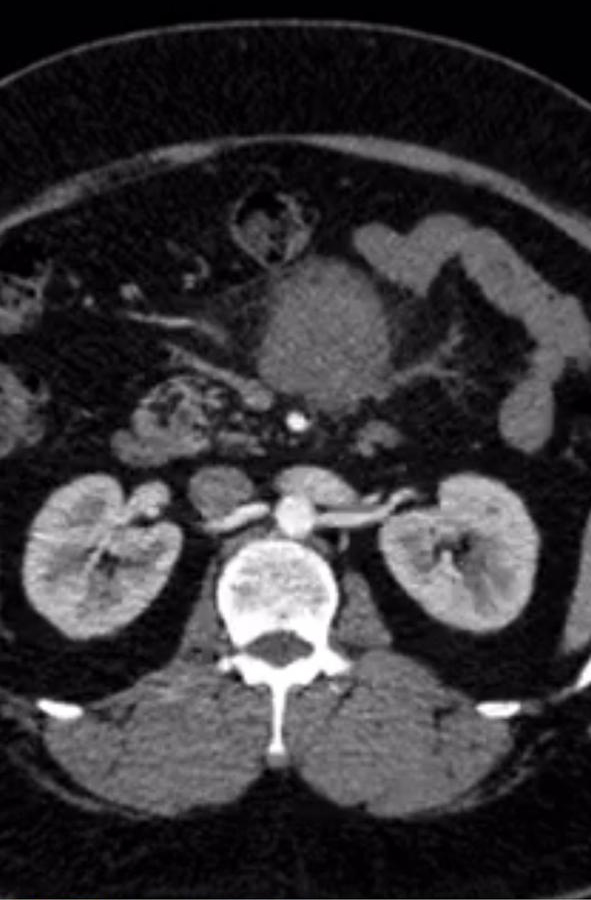

A 45 year old gentleman presented to us with vague abdominal pain. CT showed a large 6-7 cm tumor in the central mesentery sitting on important intestinal blood vessels. A CT guided biopsy proved it to be a sarcoma. The patient was obese but tumor seemed amenable for a laparoscopic surgery wherein the tumor was removed. Patient was discharged by 5th postoperative day.